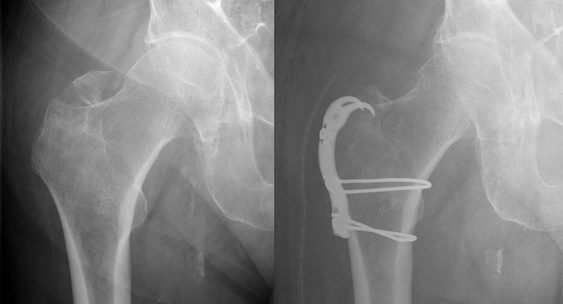

Пожилые люди, встающие ночью в туалет, нередко получают тяжелую травму — перелом шейки бедра.АМИТЕЛ